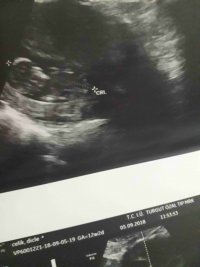

Dun malatyada verildi 12 +4 gunluk lutfen yorumlayin

nub çıkıntısının üzerinde imleç var cinsiyet anlaşılmıyor ilk sayfayı incelemenizi öneriyorum görselin kalitesi konu içinde yer alan görselle aynı olmalıdır.

Görsellerde nub çıkıntısı belli değil . Ultrasonu yapan doktor cinsiyeti hakkında bilgi vermiştir mutlaka ama şunu belirtmeden geçmeyeyim. Bu haftalarda cinsiyet tahmininde yanılma payı çok yüksek 17-19 ve 20 ci haftalarda bebeğin cinsiyetini net olarak öğrenebilirsiniz.